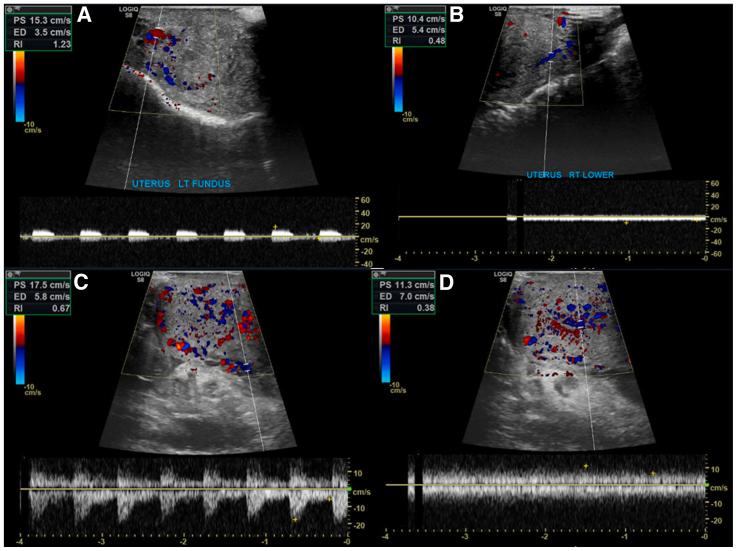

The UTx was performed by revascularizing the graft through bilateral donor internal iliac vessels (artery and vein) anastomosed end-to-side to the external iliac vessels of the recipient. The superior uterine veins were not anastomosed and were left unreconstructed. An end-to-end graft to the recipient's vaginal anastomosis was performed. After uterus reperfusion, congestion of the organ was noted, and bilateral venous thrombosis of the internal iliac veins of the graft was found. A "Y-shaped" venous jump graft was used to restore venous outflow of the left superior uterine vein and the internal iliac vein of the graft after thrombectomy.

The postoperative course was uneventful, and this UTx resulted in the delivery of a healthy infant.

To our knowledge, this is the first successful rescue technique used to restore venous outflow and save the viability and functionality of a transplanted uterus. We demonstrated that a transplanted uterus from a deceased donor with a monolateral outflow could succeed in pregnancy and the delivery of a healthy infant.